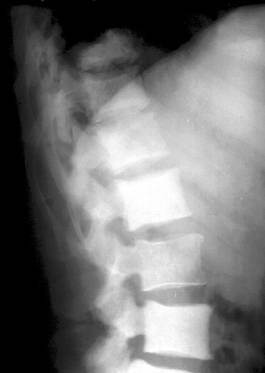

deformarea si reducerea, uneori extrema, a inaltimii corpilor vertebrali cu modificari de ax ale coloanei (cifoza pottica), dislocari, luxatii;

abcesul rece (pottic) apare ca o opacitate uni sau bilaterala ce proemina lateral, omogena, bine delimitata, depasind apofizele transverse. Abcesele din regiunea toracala medie nu migreaza la distanta si stagneaza in spatiul costovertebral sau intercostal, putand eroda coastele. Abcesele toracolombare coboara uneori pe teaca psoasilor in regiunea lombara, astfel ca vor modifica (bomba) umbra psoasului. Abcesele din regiunea cervicala deplaseaza anterior traheea si esofagul;

modificari reconstructive sub forma liniilor de demarcatie, zone de ingrosare a structurii osoase ce delimiteaza leziunea si fac sa reapara conturul vertebral care se recalcifica;

tardiv apar punti osoase intervertebrale ce demonstreaza fuziunea dintre vertebre;

evolutia fara tratament duce la distrugeri importante ale corpurilor vertebrale, aparitia sechestrelor si mari modificari de statica.